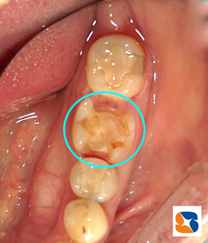

詰め物がなくなった状態

コラム「詰め物がなくなった状態」の画像